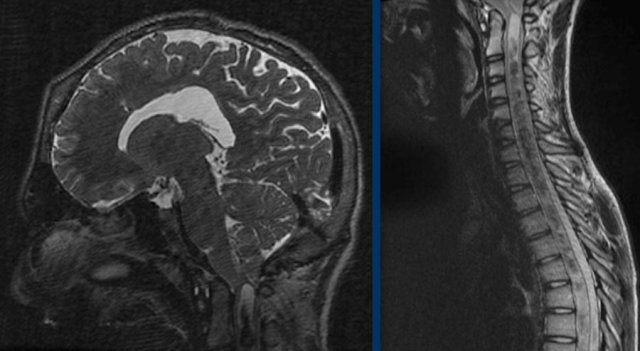

There is a risk for Chiari 1 malformation and MRI of the brain and craniocervical junction is advised.

The images are of a patient with increased intracranial pressure.

There is tonsillar herniation with severe crowding at the craniocervical junction.

This has resulted in a syrinx over the entire length of the spinal cord.